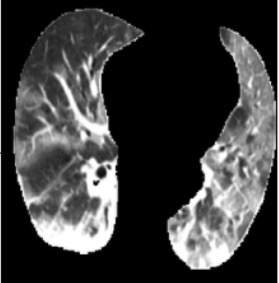

In the field of medical imaging, particularly in tasks related to early disease detection and prognosis, understanding the reasoning behind AI model predictions is imperative for assessing their reliability. Conventional explanation methods encounter challenges in identifying decisive features in medical image classifications, especially when discriminative features are subtle or not immediately evident. To address this limitation, we propose an agent model capable of generating counterfactual images that prompt different decisions when plugged into a black box model. By employing this agent model, we can uncover influential image patterns that impact the black model's final predictions. Through our methodology, we efficiently identify features that influence decisions of the deep black box. We validated our approach in the rigorous domain of medical prognosis tasks, showcasing its efficacy and potential to enhance the reliability of deep learning models in medical image classification compared to existing interpretation methods. The code will be publicly available at https://github.com/ayanglab/DiffExplainer.